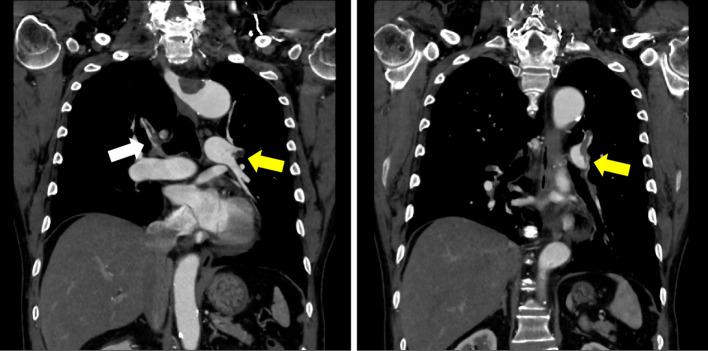

An 81-year-old man presented with shortness of breath and was referred to our hospital with suspected acute pulmonary embolism. Enhanced computed tomography revealed a right aberrant subclavian artery with a thrombosed Kommerell diverticulum (KD), as well as deep vein thrombosis in the left leg and bilateral pulmonary artery thrombosis. Thrombosis in the KD disappeared after one month of anticoagulation treatment with rivaroxaban. Thrombosis of a KD is a rare condition that may cause distal emboli and subclavian steal syndrome, although this syndrome was not present in this case. Rivaroxaban is an effective anticoagulant for treating thrombosis of a KD.

一位 81 岁男性因呼吸急促就诊,疑似急性肺栓塞,被转至我院。增强计算机断层扫描显示右侧迷走锁骨下动脉伴血栓形成的 Kommerell 憩室(KD),以及左腿深静脉血栓形成和双侧肺动脉血栓形成。利伐沙班抗凝治疗一个月后,KD 内血栓消失。KD 血栓形成是一种罕见的情况,可能导致远端栓塞和锁骨下窃血综合征,但本例中并未出现该综合征。利伐沙班是治疗 KD 血栓形成的有效抗凝药物。